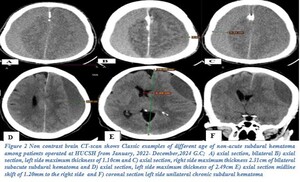

CT scan was the primary imaging modality used (87.6%). An iso-dense subdural hematoma was the most common radiological finding (54.7%), followed by a hypo-dense hematoma (42.9%). Most hematomas were unilateral (71.4%) with a left-sided predominance (41%). Most hematomas measured more than 2 cm in thickness (70.2%), and 59% demonstrated a midline shift of 5–10 mm (see Figures 2–4).

Radiologically, iso-dense hematomas were most common (54.7%), followed by hypo-dense hematomas (42.9%), with the majority showing a significant midline shift and thickness greater than 2 cm. These findings suggest delayed presentation, a common issue in low-resource settings, which result in larger hematoma volumes. The reliance on CT scans (87.6%) as the primary diagnostic tool is consistent with practices in most African neurosurgical centers due to limited MRI availability and prolonged scan times.8,9,13,22,23